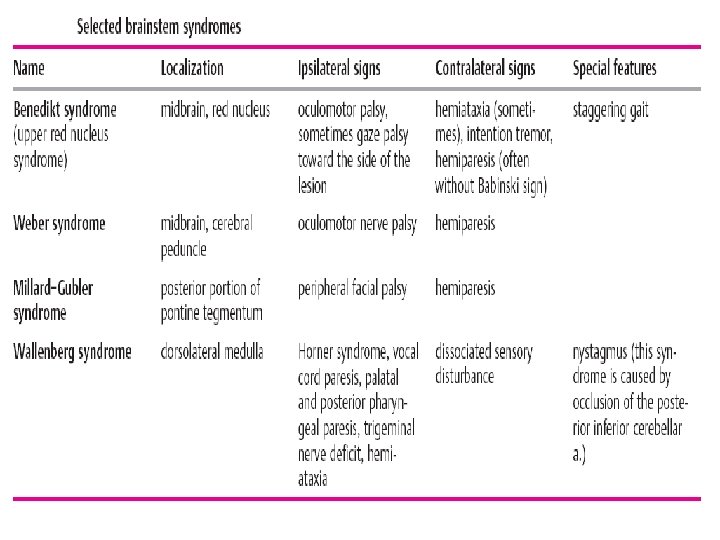

The Contents to lectures: Stroke A stroke is an acute focal or global impairment of brain function resulting from a pathological process (e. g. thrombus, embolus, vessel rupture) of the blood vessels. Its causes, in order of decreasing frequency, are ischemia (80%), spontaneous intracerebral or intraventricular hemorrhage (15%), and subarachnoid hemorrhage (5 %). The signs and symptoms of stroke are usually not specific enough to enable identification of its etiology without further diagnostic studies. CT, MRI, cerebrovascular ultrasonography, ECG, and laboratory testing are usually needed.

The Contents to lectures: Stroke A stroke is an acute focal or global impairment of brain function resulting from a pathological process (e. g. thrombus, embolus, vessel rupture) of the blood vessels. Its causes, in order of decreasing frequency, are ischemia (80%), spontaneous intracerebral or intraventricular hemorrhage (15%), and subarachnoid hemorrhage (5 %). The signs and symptoms of stroke are usually not specific enough to enable identification of its etiology without further diagnostic studies. CT, MRI, cerebrovascular ultrasonography, ECG, and laboratory testing are usually needed.

Types of infarct. There are three basic types of brain infarct, distinguished from each other by the caliber of the occluded arteries: Territorial infarcts are mainly produced by occlusions of the main trunks or major branches of cerebral arteries (cerebral macroangiopathy), which may be due to thrombosis, embolism, or other causes. The infarct includes both cortex and subcortical white matter and sometimes the basal ganglia and thalamus (Fig. 6. 12). It is usually possible to infer which vessel has been occluded from the pattern of neurological deficits that are produced.

Types of infarct. There are three basic types of brain infarct, distinguished from each other by the caliber of the occluded arteries: Territorial infarcts are mainly produced by occlusions of the main trunks or major branches of cerebral arteries (cerebral macroangiopathy), which may be due to thrombosis, embolism, or other causes. The infarct includes both cortex and subcortical white matter and sometimes the basal ganglia and thalamus (Fig. 6. 12). It is usually possible to infer which vessel has been occluded from the pattern of neurological deficits that are produced.